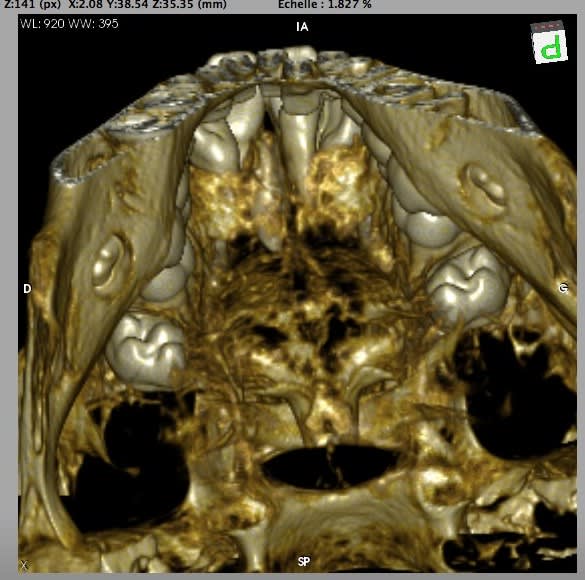

Allez, je lance le sujet, envoyez vos photos ou vidéo.

J'ai pu garder le paquet vasculo nerveux palatin antérieur. Les grincheux diront que çà sert à rien, mais j'avais le temps et je trouve çà classe :))

(le trou en palatin de la 21 c'était un odontoïde évolué en bouche que l'on ne voit pas bien sur les clichés)

- superbes tes reconstructions 3D.

Les reconstructions sont faites avec le logiciel gratuit Osirix (uniquement disponible sous MAC) à partir du CD du dentascan fourni par le radiologue.